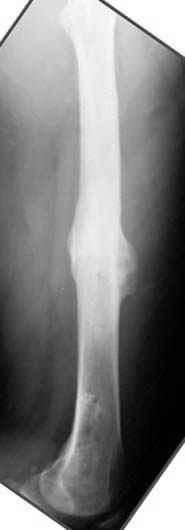

Несколько снимков из моей коллекции, чтобы разьяснить, почему мы до сих пор делаем различные варианты остеотомии.

На рисунке N1 предоперационный план лечения ложного сустава шейки бедра- линия ложного сустава, угол и направление введения импланта, клиновидная остеотомия в градусах и миллиметрах, второй снимок после коррекции, расчет, на сколько удлиняется конечность и размеры импланта;

N3 рисунок окончательный снимок, после операции моя рентгенограмма должен выглядеть примерно как эта картина. На N4 снимке клин перед удалением; N5 послеоперации 3 нед.; N6 окончательная рентгенограмма.

пластическая модель; и коррекция бедра аппаратом Илизарова.

хотя даже если бы и инфекция , то nail exchange с рассверливанием канала - вариант дебрайдмента) Я думаю, что последовательность развития событий:

Узкий к-м канал - тонкий гвоздь- усталостный перелом дистальных винтов - развитие нестабильности и как ее результат остеолиз вокруг гвоздя - деформация анатомической оси бедра. Похоже, что я понял почему аппарат, а не новый гвоздь:-)